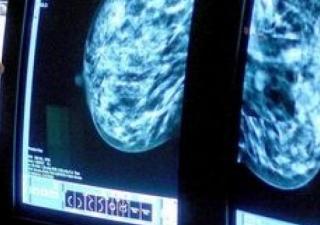

Mjekët amerikanë me sukses kanë provuar të parën “bombë të mençur” për shërimin e tumoreve të gjirit, përkatësisht kombinimin e medikamenteve të cilat ngarkesën e vet toksike e liferojnë vetëm […]